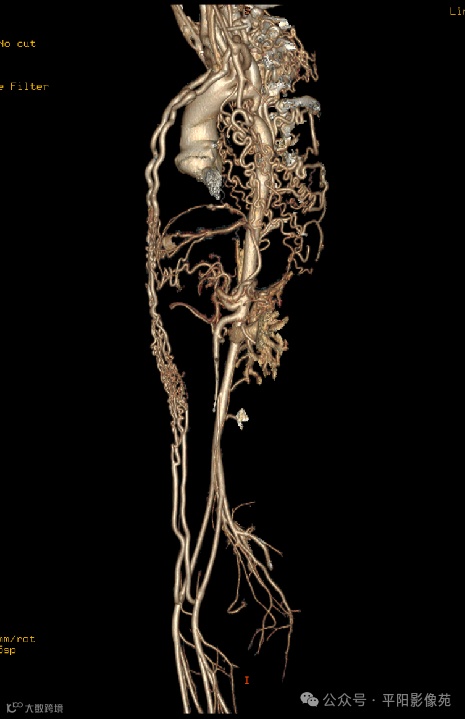

影像检查